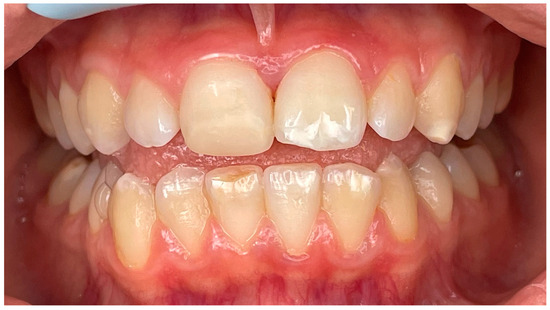

4.1. Case 1

4.2. Case 2